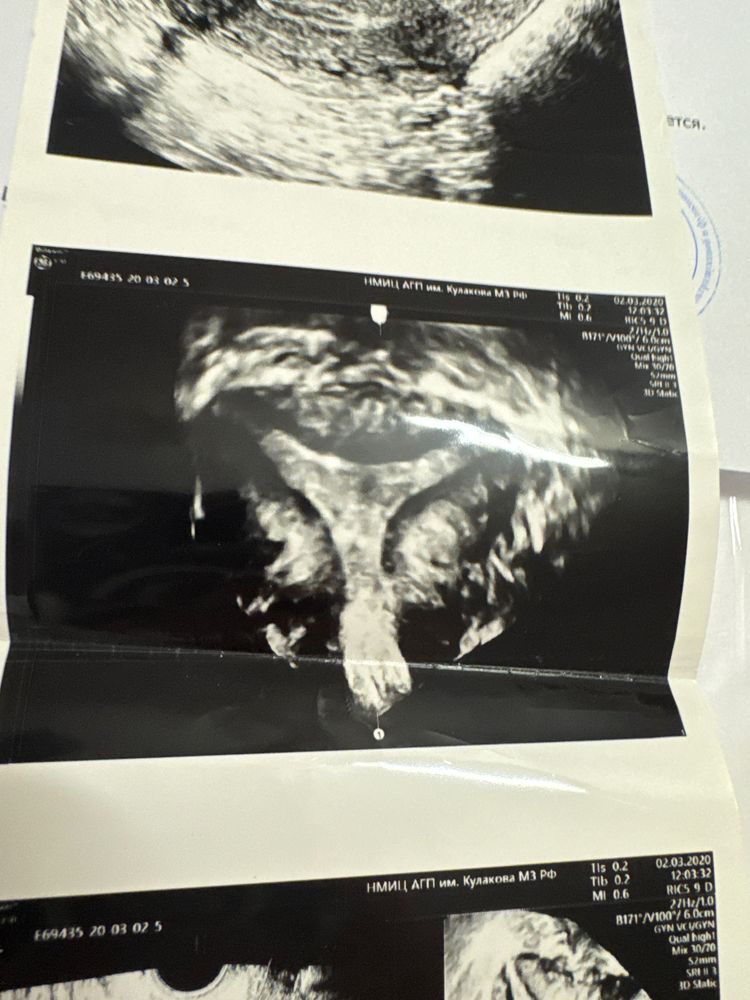

сначалп была замершая на 9 неделе, потом 2 беременности на 12-14 недель отходили воды , потом сделали операцию по рассечению перегородки. Потом 2 беременности анэмброния . Потом снова повторили операцию , мол еще сделаем коррекцию . Потом уже обращение к Каплиной. По анализам все везде идеально! Не к чему придраться. Но по клинической картине назначение: тромбоасс, метипред , клексан , Плаквенил , утрожестан . И снова замершая 7 недель . Сейчас 8 беременность, снова полная терапия . Но есть одна особенность все 8 беременность… всегда начинаются коричневые выделения, всегда . И продолжаются все беременность, сопровождаясь кровотечениями . Иногда это гематома иногда нет . Ни один супер пупер врач сказать не может откуда и зачем они идут . Но то что они начало конца я уже знаю . Прикрепляю фото своей матки . Все равно мне кажется у нее форма не такая (( помогите пожалуйста..может у кого то так было ? А то я думаю я одна такая на всей планете